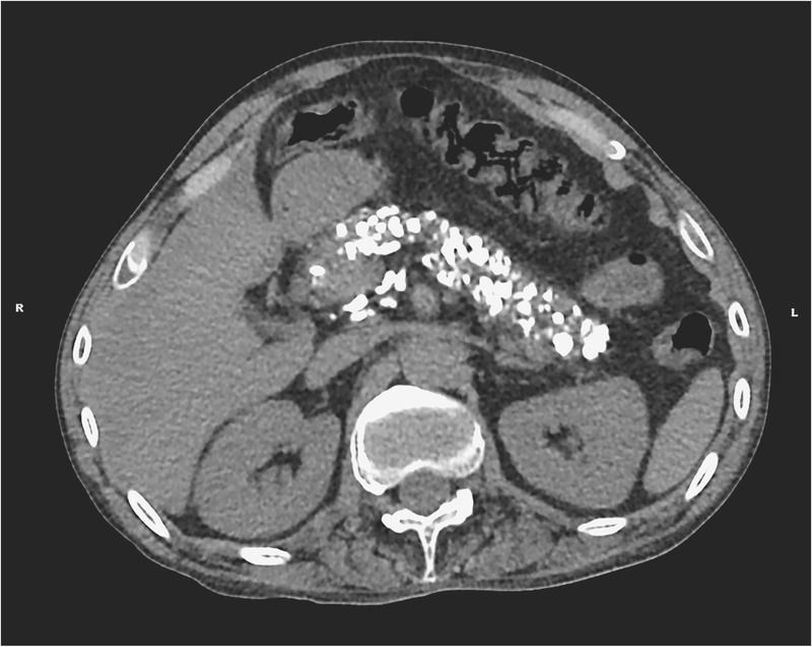

A 50-year-old man presented to the emergency department with sudden onset of hematemesis. He reported a 2-month history of epigastric pain and foul-smelling diarrhea. He had been drinking half a pint of vodka a day for 15 years. Physical examination revealed epigastric tenderness. Results of laboratory testing, including serum lipase and liver-function tests, were within normal limits. A computed tomographic scan of the abdomen showed extensive calcification of the pancreas without evidence of pancreatic edema or peripancreatic fluid collection, findings consistent with chronic calcific pancreatitis. Endoscopy revealed gastric ulcers, which were treated with acid suppression. Chronic alcoholic pancreatitis is a common cause of pancreatic calcification. Treatment of chronic pancreatitis typically includes pain management and correction of exocrine pancreatic insufficiency. This patient had an uneventful recovery; he was discharged with pancreatic enzyme supplements and was enrolled in an alcohol abuse rehabilitation program.